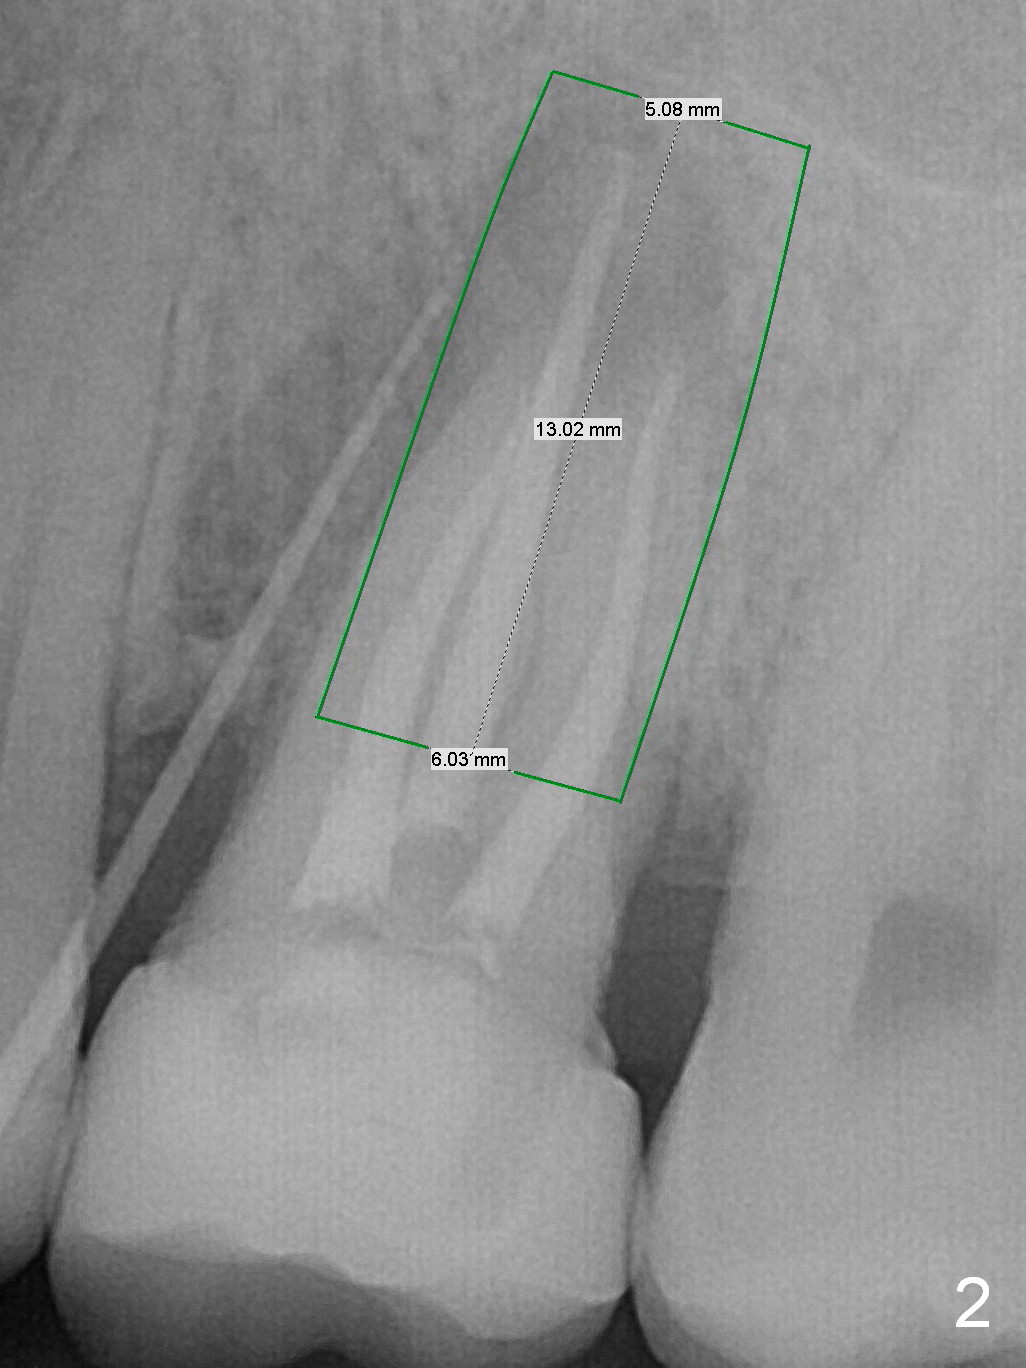

A 34-year-old man has persistent large periradicular radiolucency (Fig.1) after root canal therapy with a fistula (Fig.2). It appears that immediately after extraction (no Antibiotic) a long implant (15 or 16 mm, green outline) should be placed to bypass the bony defect with 2-point fixation (septum and sinus floor; Fig.3 (CBCT sagittal section), 4 (coronal section) red line). A shorter implant, which is placed at the septum (4-5 mm tall), is not expected to be stable. The diameter of the implant is to be determined after sequential osteotomy. The minimal will be 4 mm (Fig.5 axial section) as long as the implant or osteotomy does not perforate the palatal (P) or buccal (B) socket substantially. The bone density at the septum and the sinus floor is 1100 and 200-400 units, respectively. Drills and osteotomes (Tatum or Magic Expanders) will be used for osteotomy in these 2 segments, respectively.